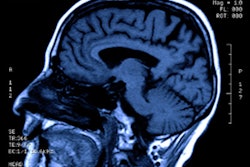

Spontaneous ICH is a dangerous clinical condition that has high disability and mortality rates, and hematoma expansion is associated with poor prognosis in these patients.

As a result, the researchers sought to create an optimal CT-based radiomics model for predicting expansion of hematoma in patients with spontaneous ICH. They first retrospectively gathered data from 235 patients at West China Hospital who had spontaneous ICH. Of these patients, 80 (34%) had hematoma expansion.

All patients in the study received noncontrast CT within six hours after symptom onset and then follow-up CT within 24 hours after onset. The researchers used 75% of the exams to train the model and set aside 25% for testing.